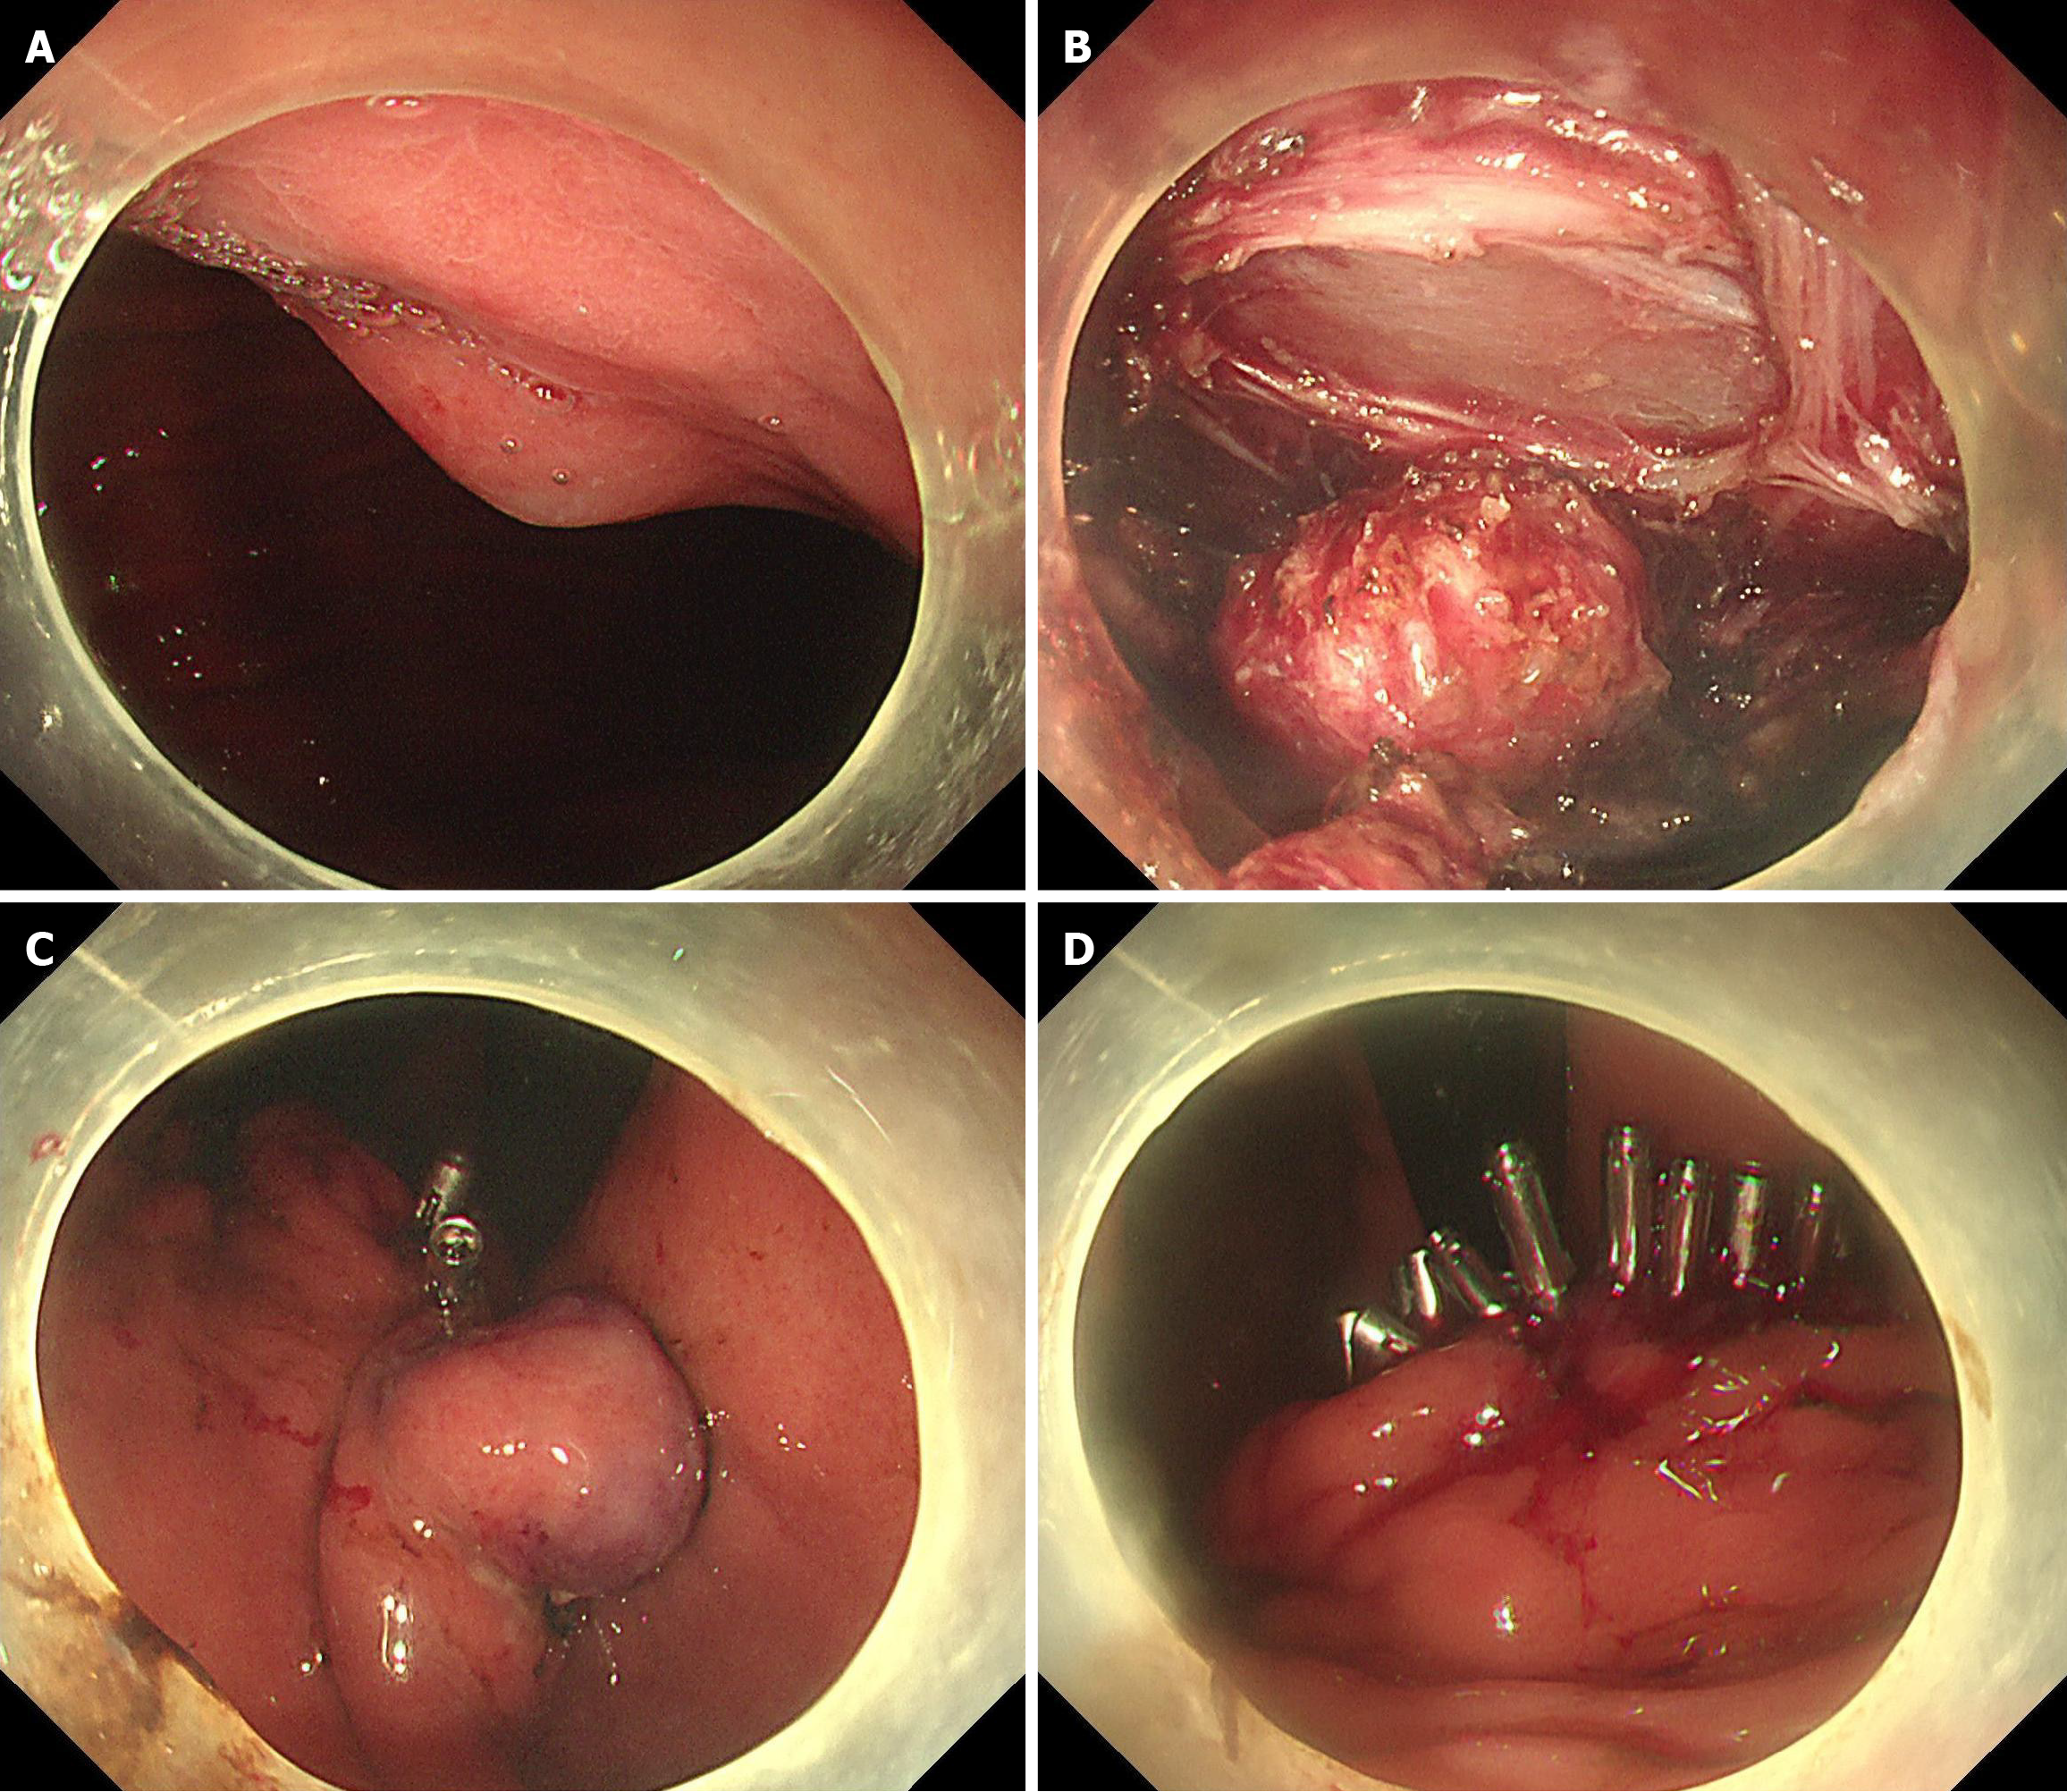

Experimental group (interrupted closure group): After performing a two-thirds circumferential full-thickness incision of the diseased gastric wall, the metal clips were performed at the proximal or distal to the wound. With minimal necessary exposure, the dissection and closure procedure were repeated until the tumor completely resected, then the defect was closed (Figure 1).